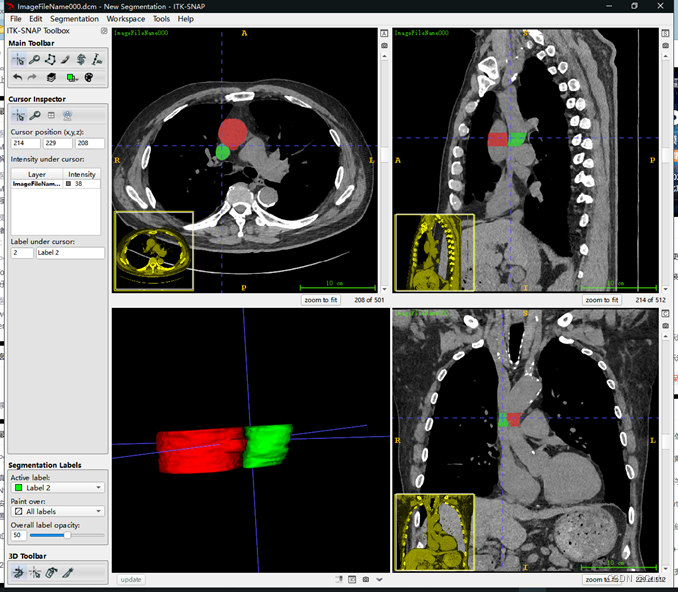

在这里我连续标注了多张,只选择了两个区域,相当于用了两种标签,效果如下

容易发现三个方向的图都有对应的标签。通过点击下图圈出的update会生成3D的标签图: